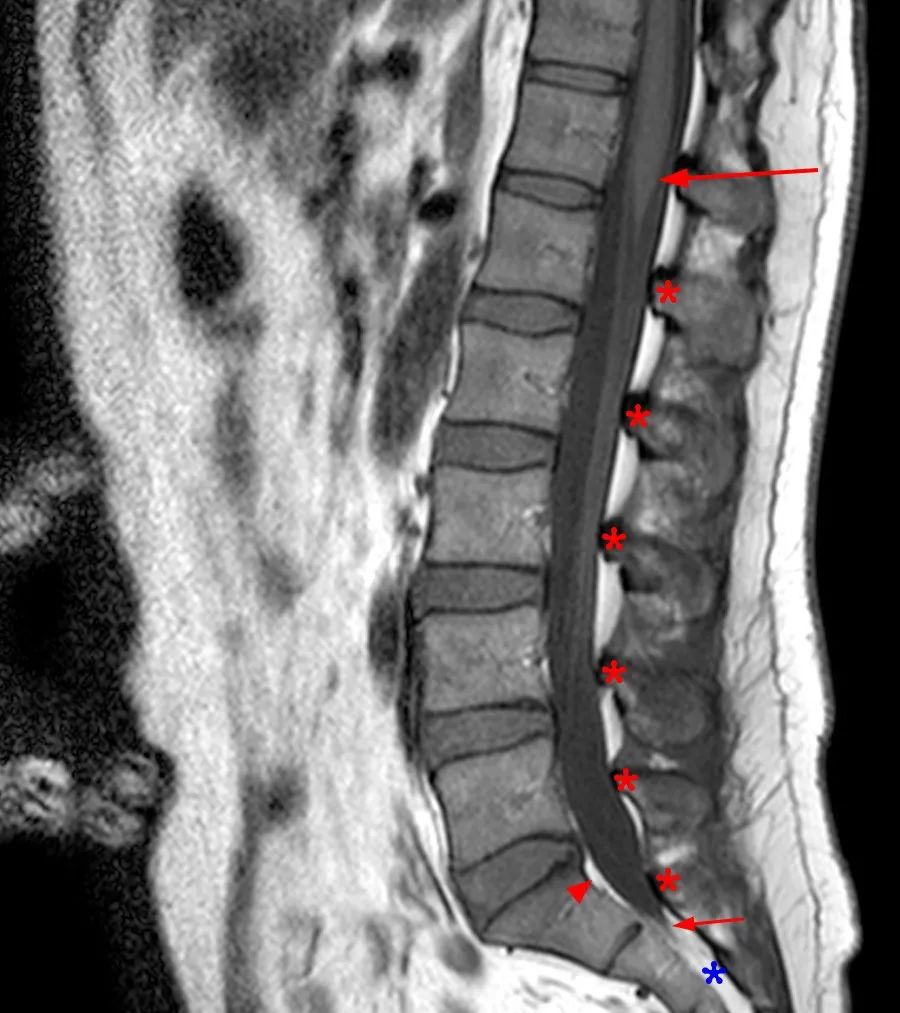

椎管内硬膜外脂肪主要分布于背侧,前缘不超过椎板前缘的连线

矢状位 T1WI 显示硬膜外脂肪组织的正常分布,在腰椎管主要分布于背侧,不连续,在每个椎体层交界处中断(星号)。S1 水平硬膜囊前方有少量正常脂肪组织(箭头),硬膜囊末端终止处,骶管内充满脂肪组织(蓝色星号)

正常的椎管内硬膜外脂肪分布,不会对椎管造成积压